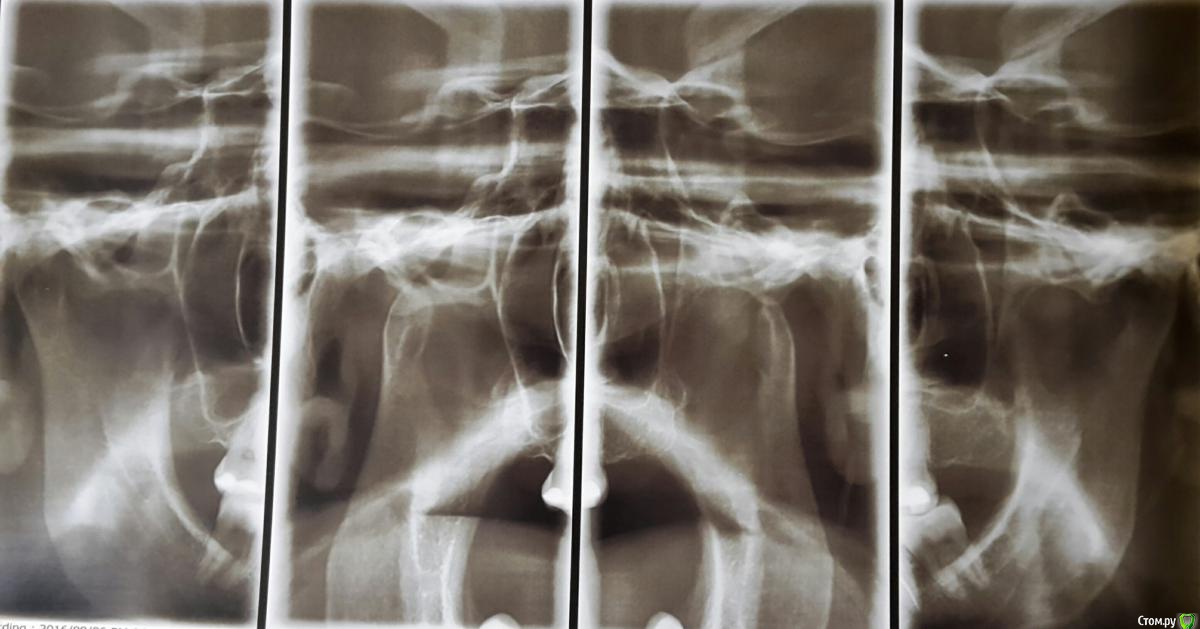

Анастасия Лазарева Опубликовано 15 сентября, 2016 Поделиться Опубликовано 15 сентября, 2016 (изменено) Добрый день, очень прошу совета по своей проблеме. Мне 28 лет. В мае этого года после 2-х часового лечения зубов очень сильно заболела челюсть слева около уха. Чувствую боль также при глотании, иногда отдает в ухо. Больно жевать, особенно жесткую пищу, рот до конца не открывается,максимум на 3-3.5 см. Дальше будто блок. До этого момента в течение многих лет челюсть слева щелкала при зевании и сильном открытии рта, но боли не было, и меня это не беспокоило.Считаю важным отметить, что долгое время я жую все время на правой стороне, тк 6 слева отсутствует с 2005 года. С болью в челюсти обратилась к врачам. Диагноз:двусторонняя болевая мышечно суставная дисфункция внчс..Также отметили неправильный прикус, смещение челюсти, тонус мышц.Предложен план лечения:1. капа. Должна устранить боль в челюсти2. Брекеты для исправления прикуса 3. Имплантация 6 слева.От таких рекомендаций голова кругом... Хотела бы спросить у опытных специалистов прокомментировать мои снимки и фото. Может Вы видите какие-то другие особенности и варианты решения проблемы,которая появилась так внезапно. Заранее очень благодарна за любые рекомендации. Изменено 15 сентября, 2016 пользователем Анастасия Лазарева Ссылка на комментарий

Skip Опубликовано 7 октября, 2016 Поделиться Опубликовано 7 октября, 2016 Хотя он пугает. ..что значит невправляемый? И что посоветуете с этим делать? Там слева гораздо всё серьёзней и похоже на дегенеративный остеоартрит.В этом случае КТ суставов было бы информативней, чем представленные снимки. Ссылка на комментарий